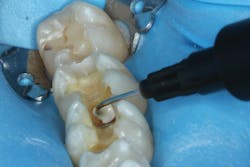

After removing the previous restorations, the distal axial wall of tooth No. 30 and the mesial axial wall of No. 31 had deep caries (figure 2). TheraCal LC (Bisco Dental)—a light-cured, resin-based liner containing calcium silicate (the active ingredient of MTA)—was placed over these areas of deep caries. A thin layer of the material was placed just at the areas of deep caries (figure 3) and light cured. Layers should be kept thin to ensure that the entire bulk of this opaque material cures, and placement should be limited to areas where needed in order to use the surrounding dentin for adhesive bonding. The dentin should be moist but not overly wet when TheraCal LC is applied to ensure that the material “sticks” to the tooth. Because this material is resin based, it is not necessary to cover this material with a separate resin-modified glass ionomer (RMGI) liner.

Figure 3: Placement of resin-based, light-cured calcium silicate liner (TheraCal LC; Bisco Dental)